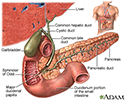

The health care provider will inject a radioactive chemical called a gamma-emitting tracer into a vein. This material collects mostly in the liver. It will then flow with bile into the gallbladder and then through the common bile duct to the duodenum or small intestine.

This test is very good for detecting a sudden infection of the gallbladder or blockage of a bile duct. It is also helpful in determining whether there is a complication of a transplanted liver or a leak after the gallbladder has been surgically removed.